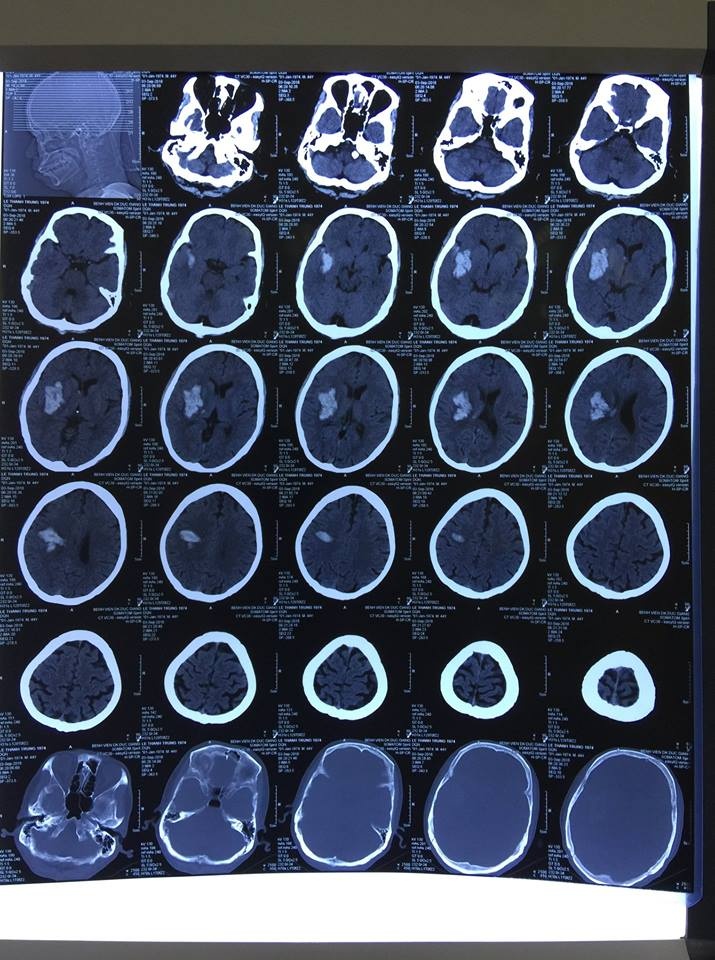

Tại Bệnh viện Đa khoa Đức Giang (Hà Nội), anh Lê Thành Công (đã đổi tên, 44 tuổi, Gia Lâm, Hà Nội) nhập viện trong tình trạng đau đầu, nói ngọng. Các kết quả chụp CT sọ não cho thấy anh có khối máu tụ trong não, cần phải theo dõi sát. Tuy nhiên, chỉ sau một thời gian ngắn, sức khỏe anh Công chuyển biến xấu, rơi vào trạng thái hôn mê, liệt nửa người trái.

Ngay lập tức, các bác sĩ đã chụp lại CT sọ não, kết quả cho thấy khối máu tụ trong não đã lan rộng, kích thước to gấp 3-4 lần gây chèn ép các tổ chức xung quanh.

| Hình ảnh khối máu tụ trong não anh Công đã lan rộng, kích thước to gấp 3-4 lần gây chèn ép các tổ chức xung quanh. Ảnh: T.N. |